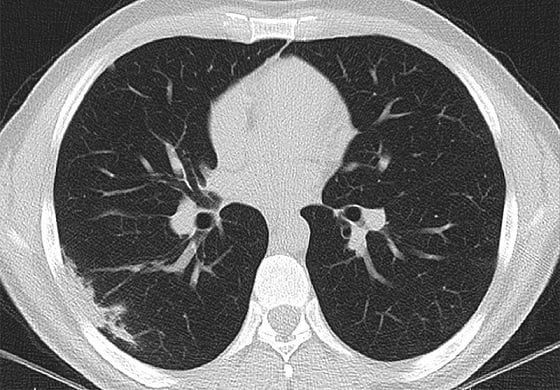

만성피로, 두통, 흉통(가슴 통증) 등 코로나19(COVID-19)를 앓다 완치 판정을 받고 퇴원한 일부 환자들 사이에서 오랜 기간 다양한 후유증을 겪는 사례가 잇따라 보고된 가운데, 미국 영상의학과 전문의들이 코로나19에 의한 폐 손상은 초기 감염 후에도 몇 주 간 지속 된다는 사실을 CT(컴퓨터단층촬영) 관찰을 통해 알아냈다.

17일 한국과학기자협회의 ‘코로나19 연구 속보’에 따르면 미국 서던캘리포니아대 알리 골람레자네자드 교수 연구팀이 코로나19에 걸린 환자 33명을 대상으로 CT를 이용해 한 달간 폐를 관찰했다. 코로나19는 호흡기 전염병이므로 폐는 장기적 손상을 확인할 가장 확실한 장기다. 연구 결과 폐 세포의 3분의 1 이상이 사멸해 흉터로 남았다. 연구팀은 “코로나를 앓거나 회복한 뒤에도 폐에 장기적 손상이 가해진다”면서 “상태가 호전된 후에도 호흡에 어려움을 겪는 경우가 많은 이유”라고 설명했다.

골람레자네자드 교수는 “대다수 감염된 사람들이 병원에 입원하지 않기 때문에 이런 폐 손상을 확인할 가능성은 10% 미만일 것”이라고 말했다. 이는 지금까지 전 세계적으로 2900만명이 넘는 감염자가 나온 것으로 알려진 상황에서 최소 수십만 명이 비슷한 상황을 겪고 있을 것이란 의미다.